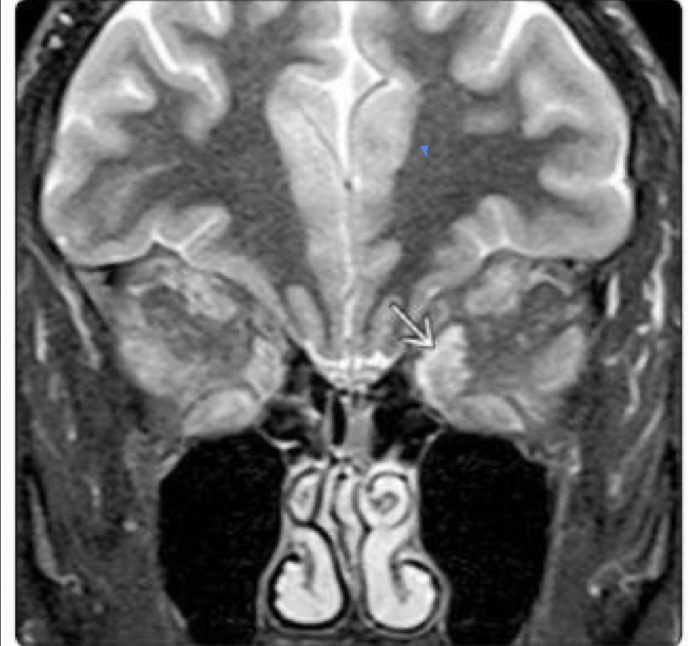

16

Q

Evaluar implicaciones intra

y extra oculares así como

intracraneales

Se puede identificar hemorragia

retinal

Mejor caracterizacion de lesion

pineal